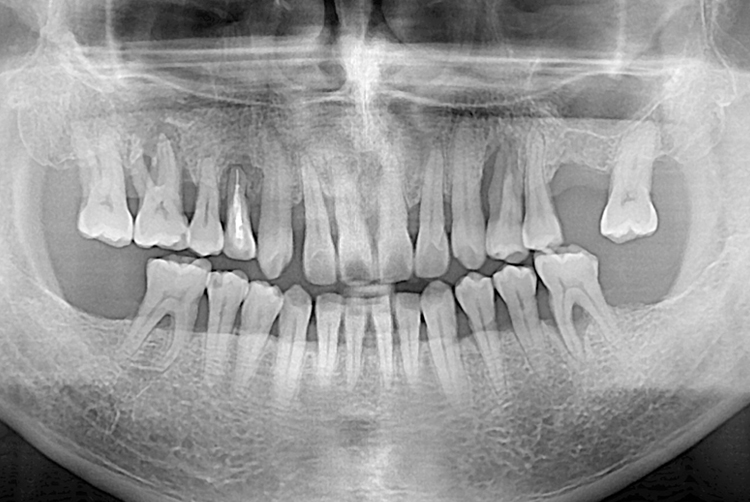

[임플란트] 임플란트

치료전 : 2019-10-16